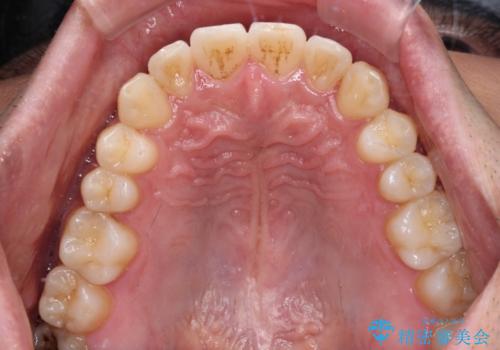

ワイヤー装置での上下前歯の部分矯正

部分矯正は咬み合わせが不安定になったり、スペースができてしまったりと、適用となる患者様は極めて限られますが、こちらの方はスムーズに治療を終えることができました。